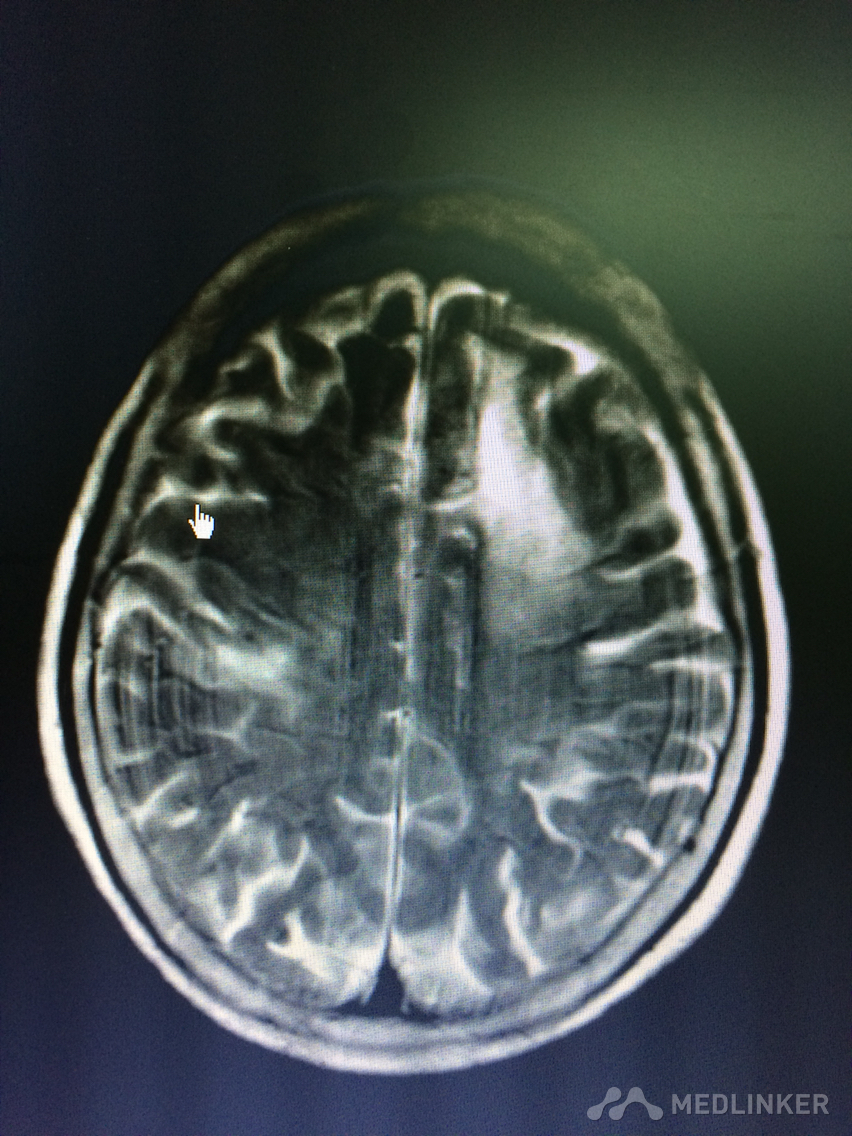

看看这MRI,奇怪啊,快来帮忙看看?

患者78岁老年女性,以精神行为异常和认知障碍为主要表现